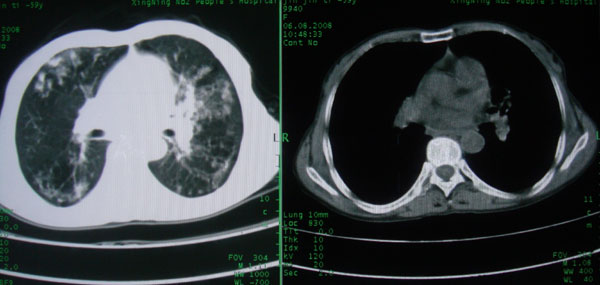

标题: CT15046:F59Y,咳嗽间断咳血丝痰就诊. [打印本页]

标题: CT15046:F59Y,咳嗽间断咳血丝痰就诊.

咳嗽\间断咳血丝痰就诊.